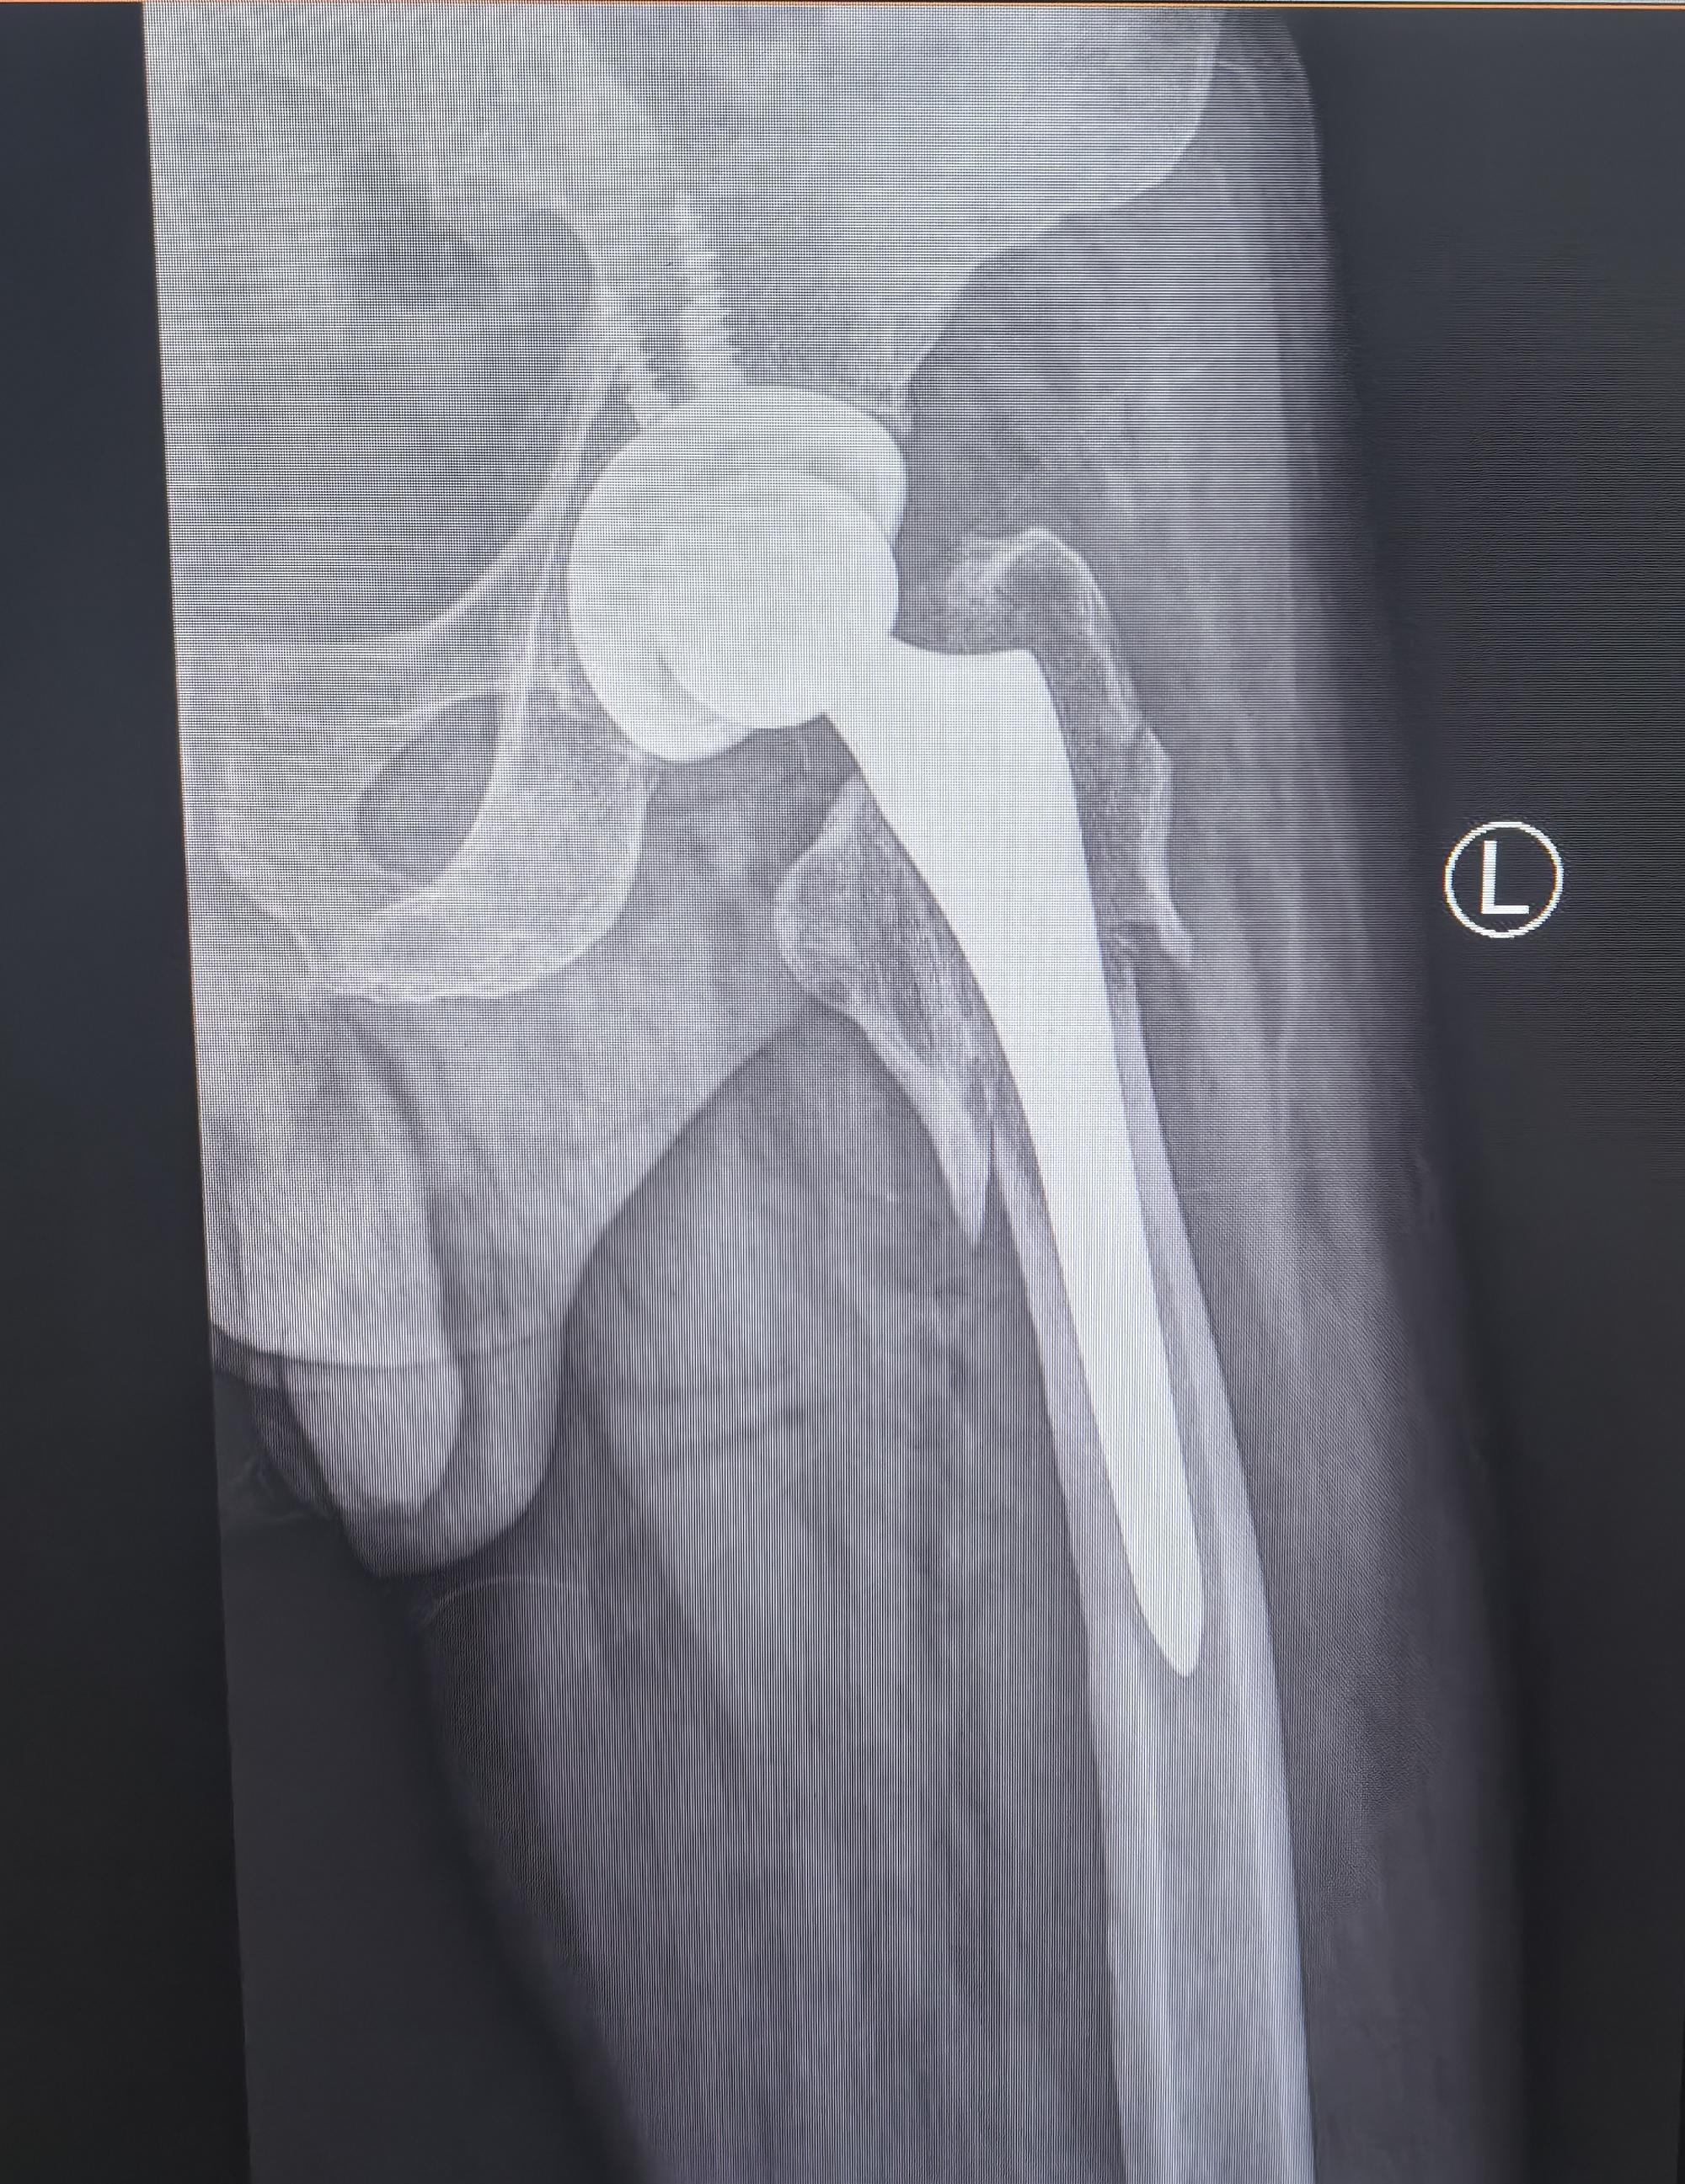

髋关节置换术后假体周围骨折。老年人一定要重视骨质疏松的预防(抗骨质疏松、适当运动、防跌倒),避免出现假体周围骨折的情况,虽然可以手术治疗,两天后也可以下床,但是创伤要比第一次大。